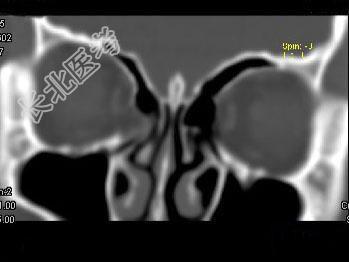

- 单项选择题女,25岁, 因眼部外伤来院就诊,CT如图所示, 最可能的诊断是 ( )

A、右侧颧弓骨折伴筛窦积血

B、右眼眶内侧壁骨折伴筛窦积血

C、右眼眶外侧壁骨折伴筛窦积血

D、右眼眶内外侧壁骨折伴筛窦积血

E、蝶骨骨折伴筛窦积血